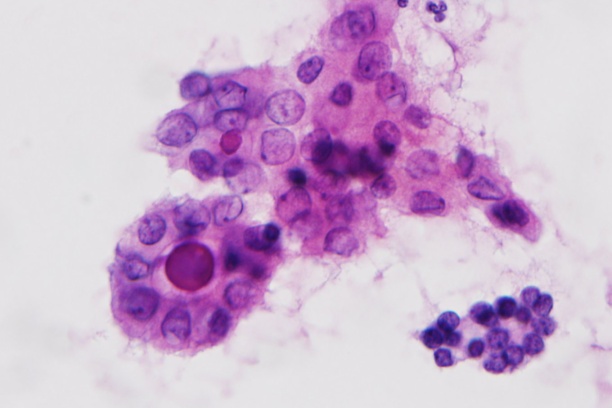

The Weiss laboratory is focused on understanding the molecular and immunologic mechanisms of thyroid cancer invasion and metastasis. While most thyroid cancer patients respond well to standard therapy, there are few options for those with widely metastatic or recurrent disease. Predicting which patients will have aggressive disease and treating those patients is an important goal in the field. The goal of the laboratory is to understand the signaling mechanisms and immune microenvironment responsible for the aggressive malignant behaviors of metastatic and recurrent disease. Projects include defining the role of Wnt signaling within the current molecular landscape of papillary thyroid carcinoma. The laboratory also uses computational immunogenomics to define the immunologic microenvironment within aggressive thyroid cancer subtypes to improve treatment and malignancy risk prediction at the time of biopsy.